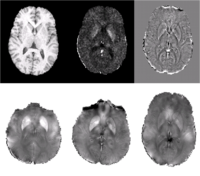

Quantifying magnetic susceptibility in the brain from the phase of the MR signal provides a non-invasive means for measuring the accumulation of iron believed to occur with aging and neurodegenerative disease. Phase observations from local susceptibility distributions, however, are corrupted by external biasfields, which may be identical to the sources of interest. Furthermore, limited observations of the phase makes the inversion ill-posed. We describe a variational approach to susceptibility estimation that incorporates a tissue-air atlas to resolve ambiguity in the forward model, while eliminating additional biasfields through application of the Laplacian. Results show qualitative improvement over two methods commonly used to infer underlying susceptibility values, and quantitative susceptibility estimates show better correlation with postmortem iron concentrations than competing methods.

We present a variational approach for Atlas-based Susceptibility Mapping (ASM) that performs simultaneous susceptibility estimation and biasfield removal using the Laplacian operator and a tissue-air susceptibility atlas. In [7, 8, 6] it was shown that applying the Laplacian to the observed field eliminates non-local biasfields due to mis-set shims and remote susceptibility distributions (ie. the neck/chest). In this method, large deviations from the susceptibility atlas are penalized, discouraging the estimation of artifactual susceptibility eigenfunctions in regions near tissue-air boundaries where the Laplacian may not be sufficient to eliminate the contribution of non-local sources and substantial signal loss corrupts the observed field. Agreement of predicted and observed fields within the brain is also enforced, but deviations in estimated susceptibility values outside the brain are not penalized, allowing values at the boundary to vary from the atlas-based prior to account for unmodeled external field sources (ie. shims).

Results